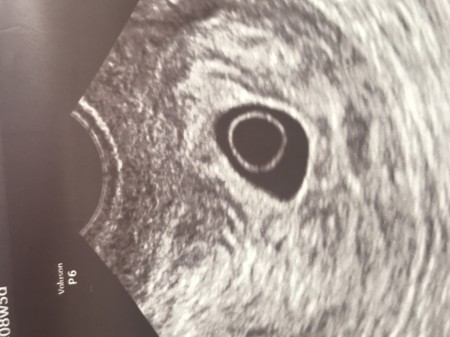

Kese Var Bebek Gorunmuyor Hamilelikte Bebek Sagligi

Kese Var Bebek Yok Hamilelik Donemi Genel

Kese Var Bebek Yok